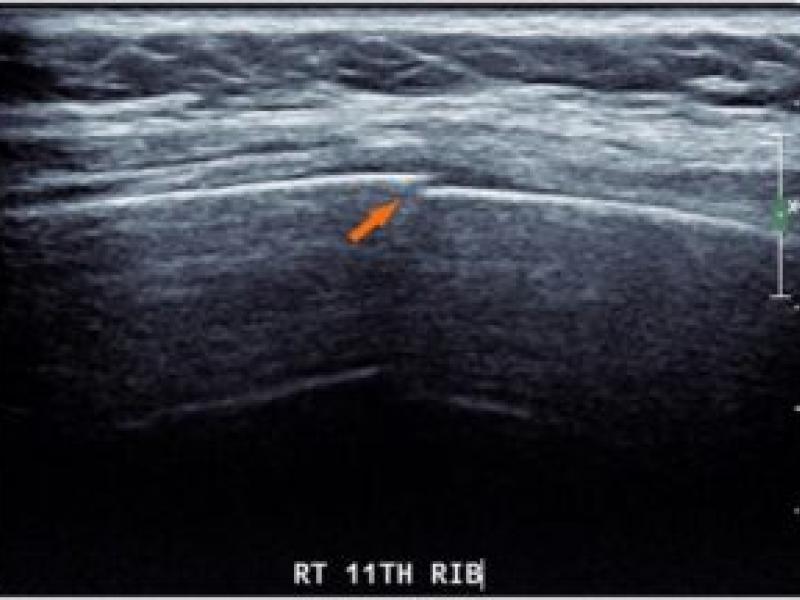

Rib Fractures part 2/Serratus Anterior Nerve Block: By Dr. DeMarzo

Rib fractures can be an incredibly painful condition for